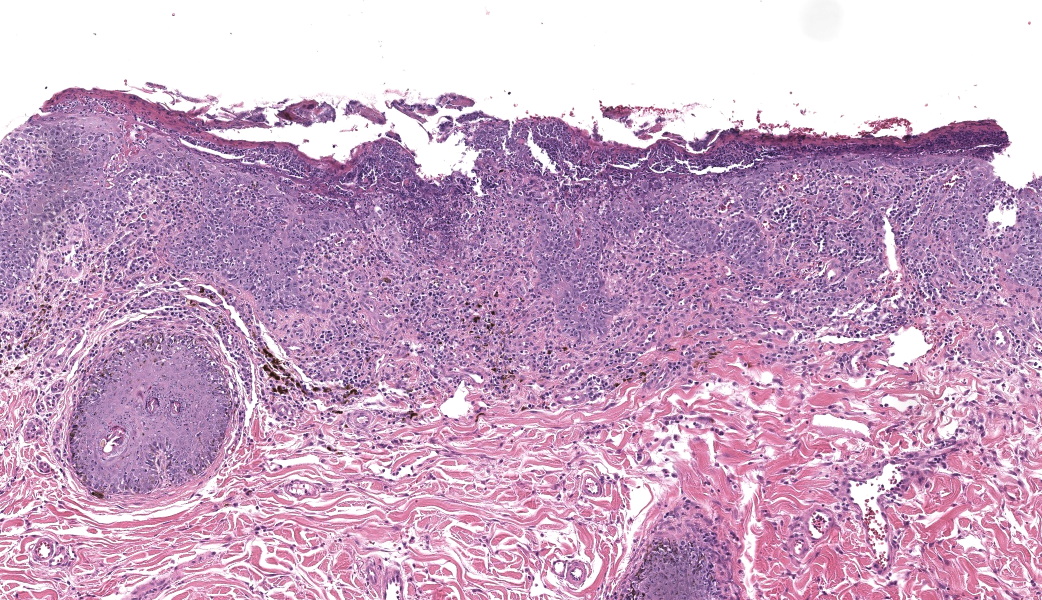

Haired skin. Alle the biopsies are histologically similar. The superficial and mid dermis is obscured by a moderate to severe inflammatory infiltrate, often obscuring the dermo-epidermal junction. The inflammatory infiltrate is represented by a prevalence of lymphocytes and plasma cells, macrophages occasionally engulfing melanin (melanophages), and rare neutrophils. The epidermis is moderately thickened (irregular hyperplasia), with mild intercellular edema (spongiosis) and severe thickening of the stratum corneum by predominantly nucleated (parakeratotic hyperkeratosis) or less frequently non-nucleated keratin (orthokeratotic hyperkeratosis). Numerous apoptotic figures are observed throughout the epidermis, occasionally surrounded by lymphocytic satellitosis. Similar lesions are observed in the hair follicles. There is multifocal erosion or ulceration of the epidermis; the ulcerated areas are obscured by serocellular crusts.Contributor's Morphologic Diagnoses:

Histologically, EM has the features of a cytotoxic (interface) dermatitis. Necrotic keratinocytes are present throughout the epidermis and the adnexal epithelia, often associated with lymphocytic satellitosis. The dermopidermal junction is obscured by lymphocytes and macrophages. Basal keratinocytes could be degenerated.3,5,6 Hyperkeratosis and parakeratosis are commonly seen in canine EM, as opposed to human EM, and may be severe in persistent forms of EM.6 This latter form is called “hyperkeratotic EM”.1

This classic case of erythema multiforme (EM) was much appreciated by participants as it stimulated great discussion on EM and other top differentials, cytotoxic dermatitis pathogenesis, and a handful of “boards-worthy” information. The contributor’s well-written and thorough comment covers much of what was discussed in conference related to the differences between the human and canine manifestations of EM, so focus will be placed on other major discussion points.The major histologic features to help differentiate EM from other conditions are the presence of suprabasilar and transepidermal apoptosis of keratinocytes and satellitosis of lymphocytes around affected keratinocytes.5 Note, however, that if lymphocytes are instead aggregating in and near the epidermis rather than just hovering around affected keratinocytes, epitheliotropic T-cell lymphoma should rise on the differential list. In EM, epithelial dysplasia may also be seen secondary to the concurrent inflammation and necrosis. The same features of transepidermal apoptosis and lymphocyte satellitosis can also be seen in the follicular epithelium, not just in the epidermis! Follicular epithelium may also exhibit hyperpigmentation and vacuolation secondary to inflammation. Parakeratotic hyperkeratosis is often seen in the hyperkeratotic form of EM but is not considered a key diagnostic feature of EM in general.1,5